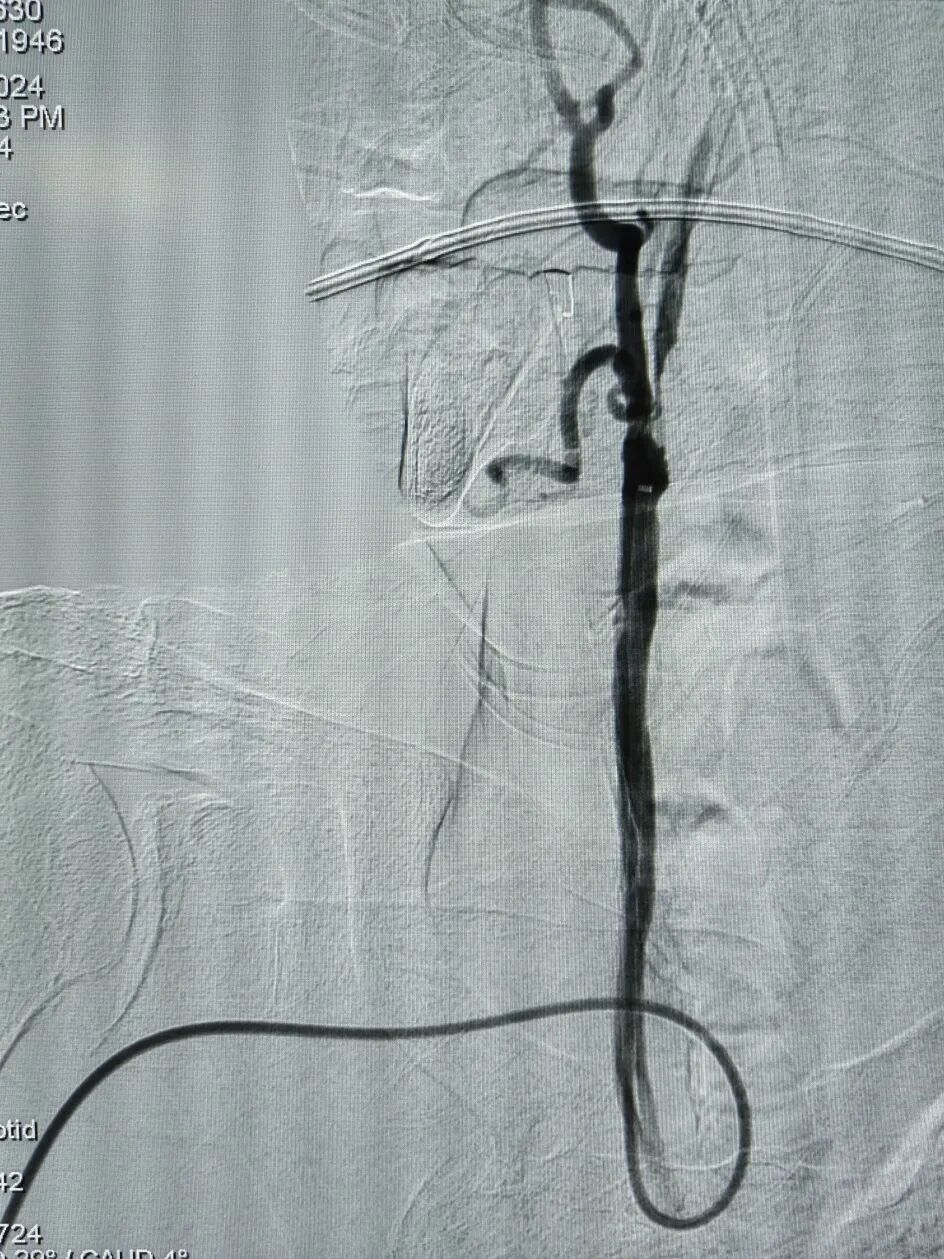

手术过程

经右侧桡动脉穿刺置入7F 薄壁鞘,畅医达 Calvada 5F 内腔0.072'' 导管鞘同轴125cm 5F 西蒙Ⅱ导管,在0.035'' 导丝引导下顺利到达右侧颈总动脉远端,小球囊预扩后,送入5mm 保护伞,4.0mm×30mm 球囊扩张后置入7mm×40mm 颈动脉支架。